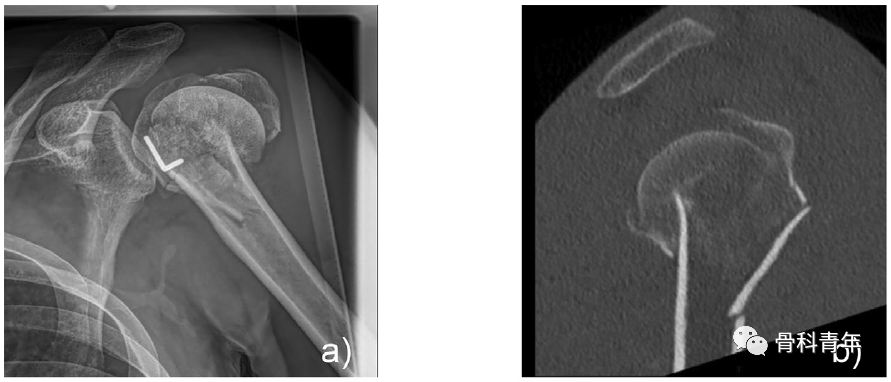

典型病例:a/b,术前X线及CT;e/f,术后4月复查。